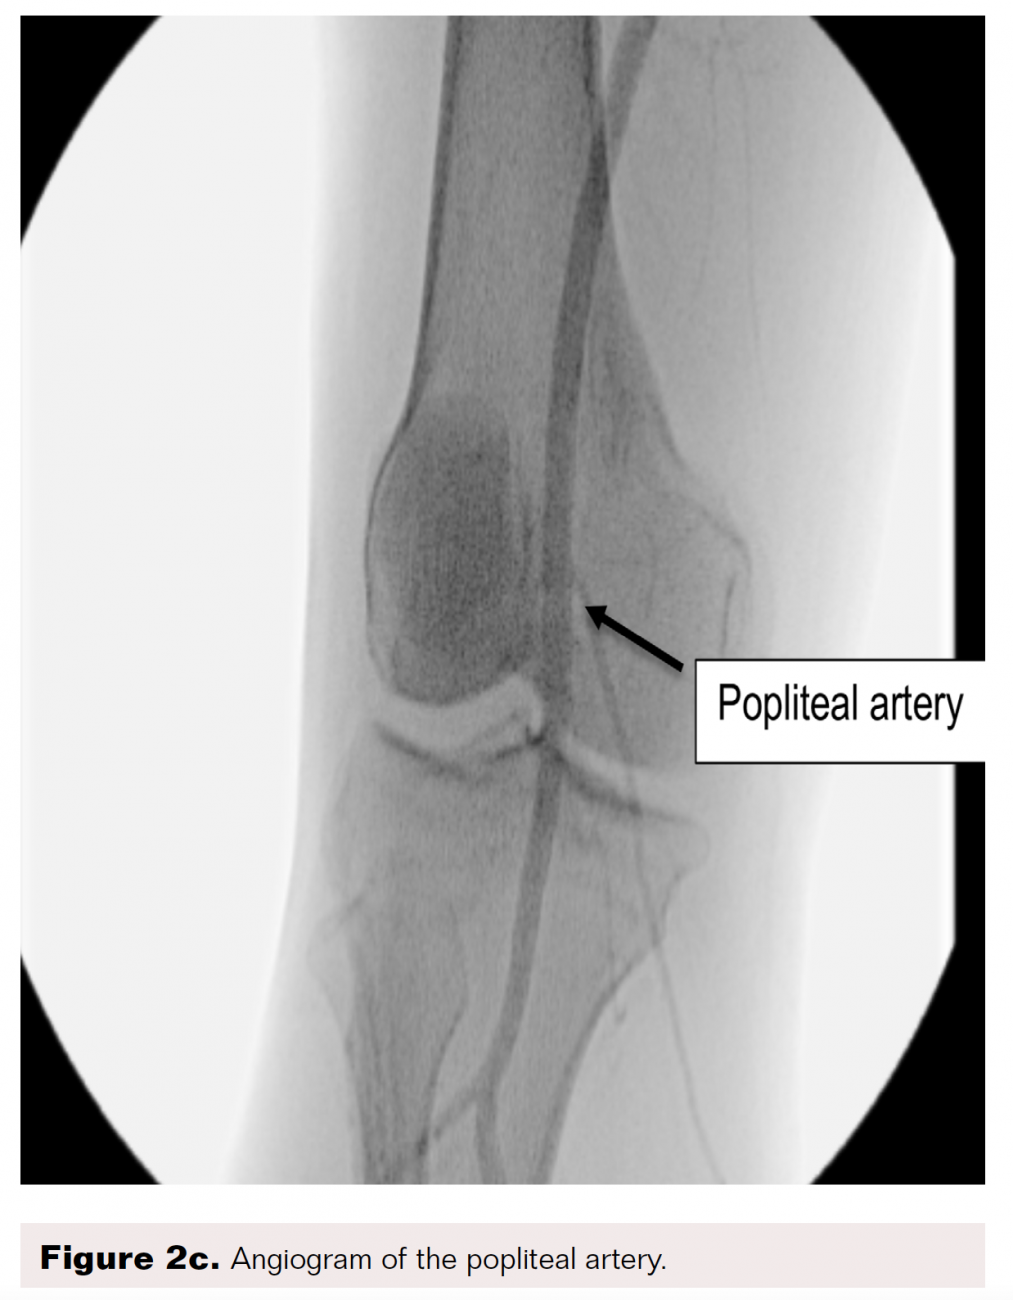

From www.hmpgloballearningnetwork.com

PedalPlantar Loop in Lower Extremity Angiographic Interventions Pedal Disease Definition peripheral artery disease (pad) is a common condition in which narrowed arteries reduce blood flow to the arms or. peripheral vascular disease (pvd) includes peripheral arterial disease (pad) and venous disease. Pad is a chronic progressive. atherosclerotic lower extremity artery occlusive disease—commonly referred to as peripheral artery disease (pad)—affects. whenever severe pain occurs at the beginning. Pedal Disease Definition.